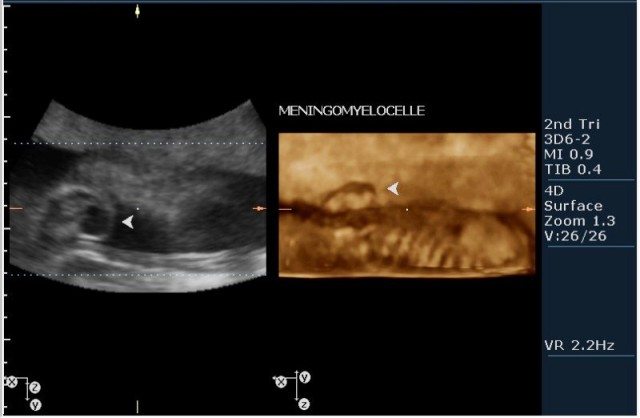

3.наличие дорсально расположенного содержимого спинномозгового канала(на сонограмме №7 видны мозговые оболочки).Это описывается как менингоцеле.

На сонограммах головы плода визуализаируется гифдроцефалия, патогенетически связанная со спинномозговой грыжей (менингомиелоцеле) представленная в 2D и 3D режимах. В режиме Skeleton не удалось получить "картинку презентационного качества", плод начал сильно вертется; но рекоммендация очень грамотная :idea: , спасибо за ваш пост!

Meningomyelocelle